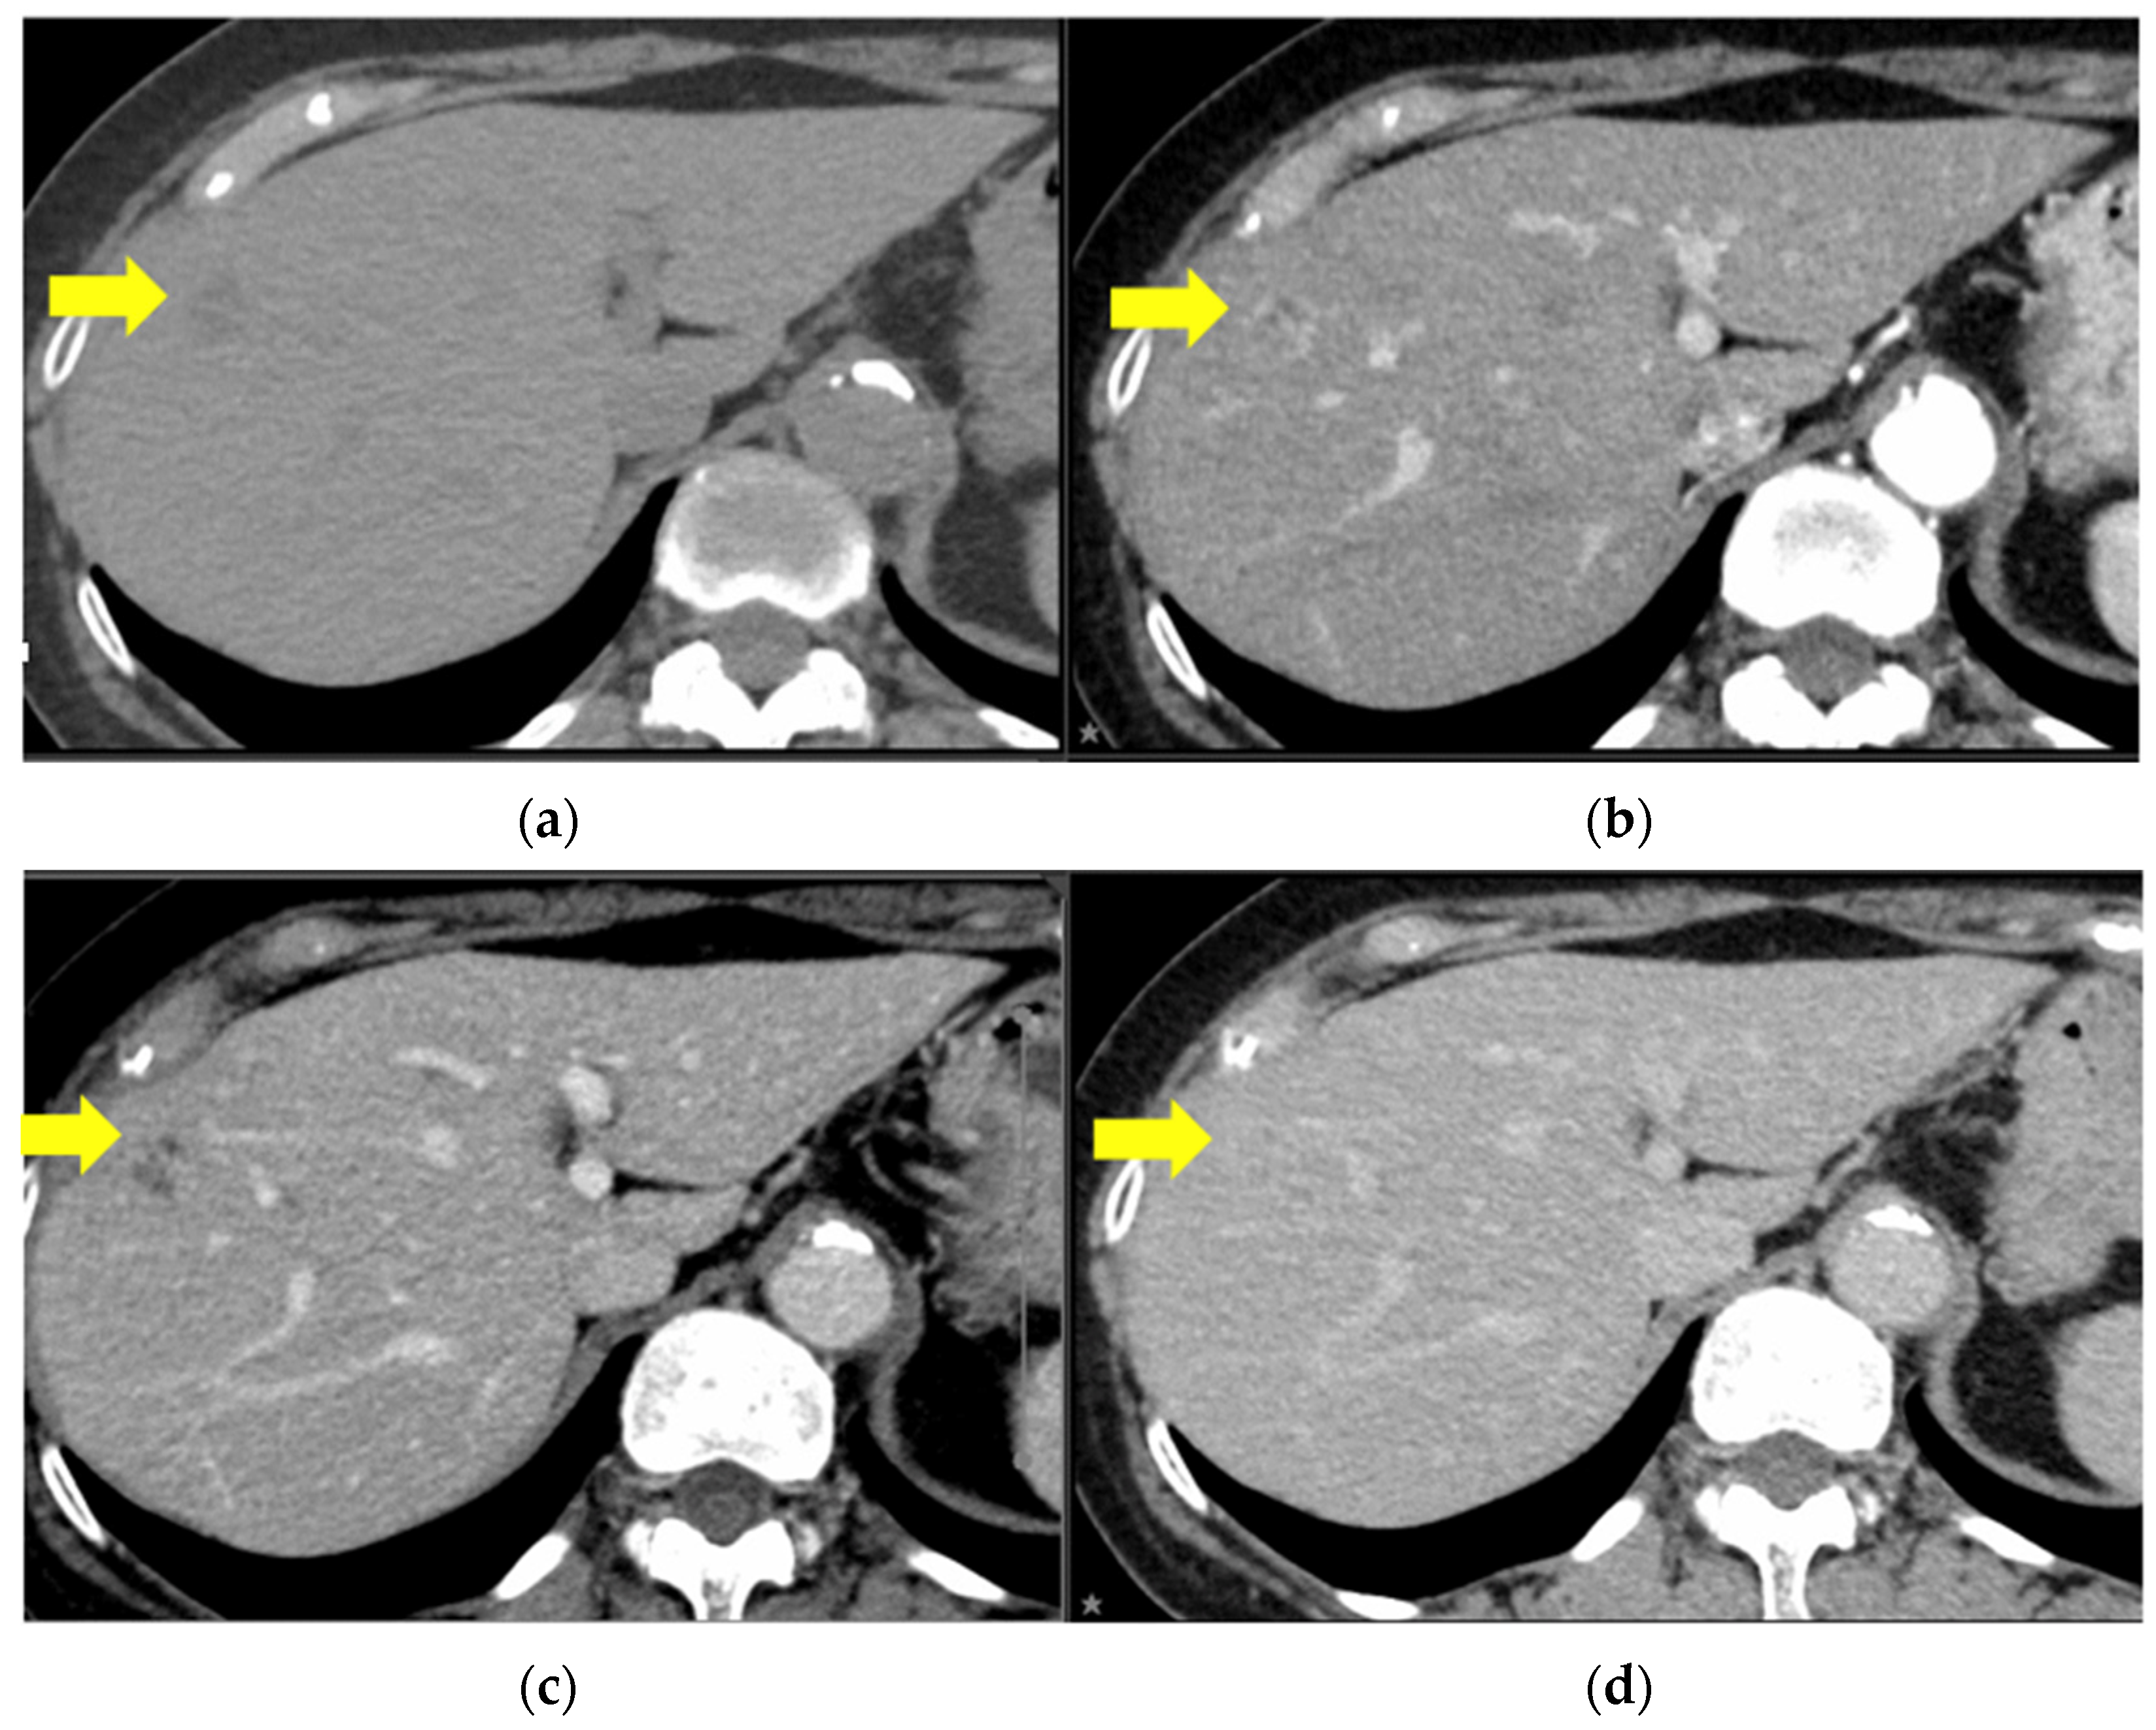

2. Case Report